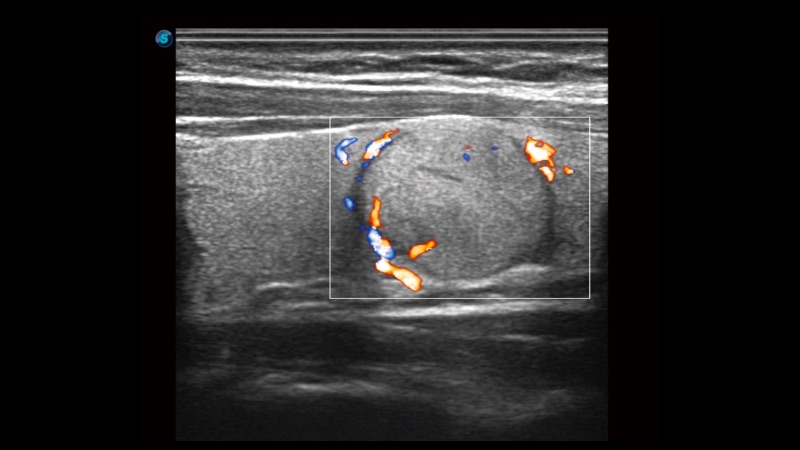

高分辨率血流成像技術提高了對低速血流信號的檢測能力。在提高空間分辨率的同時,也克服了血流外溢現象,為用戶提供更加真實的血流動力學信息。